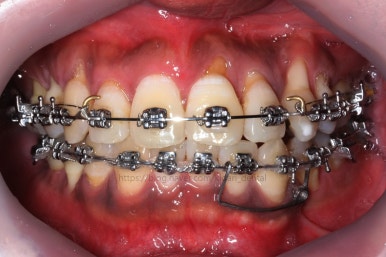

부산치아교정 키다리아저씨치과에 처음 내원 당시의 입안 모습입니다.

여러 가지 문제점이 있는데 하나씩 살펴볼게요.

치열이 많이 삐뚤하네요.

많이 삐뚠 상태에서 장기간 사용하다 보면 안좋은 방향으로 치아가 힘을 받게 되고 마모나 치아 목부분 패임이 심해집니다.

양치가 힘들어요. 양치가 힘들다 보니 세게 닦게 되고 치아 손상은 더 심해져요. 25세의 나이였는데 나이에 비해서 치아나이가 굉장히 많은거죠.

화살표 부분에 원래 송곳니가 있어야 되는데 보이질 않네요. 결손치아일 수도 있고 매복치아일 수도 있겠어요.

왼쪽 위 어금니도 한 개가 없어서 빈공간이 약간 남아있어요.

왼쪽 아래 작은 어금니는 아래쪽으로 많이 꺼져있네요.